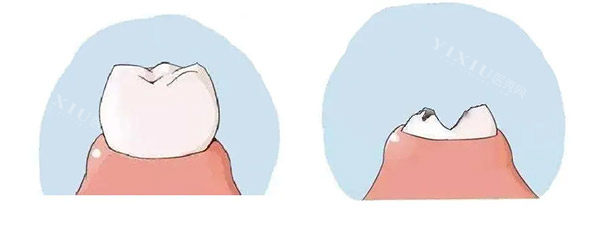

特色项目1:即刻种植——小切口,疗养时间短

传统种植牙需要等3-6个月骨愈合再种牙,哲德口腔的即刻种植技术能在拔牙后直接种入植体,减少复诊次数。适合单颗/多颗缺牙、牙槽骨条件较好的患者。之前有位50多岁的阿姨分享,她拔了两颗后牙直接种,手术用的是瑞典诺贝尔种植体,医生操作精细,术后3天就正常吃饭,现在啃苹果都没问题,“比想象中轻松多了”。